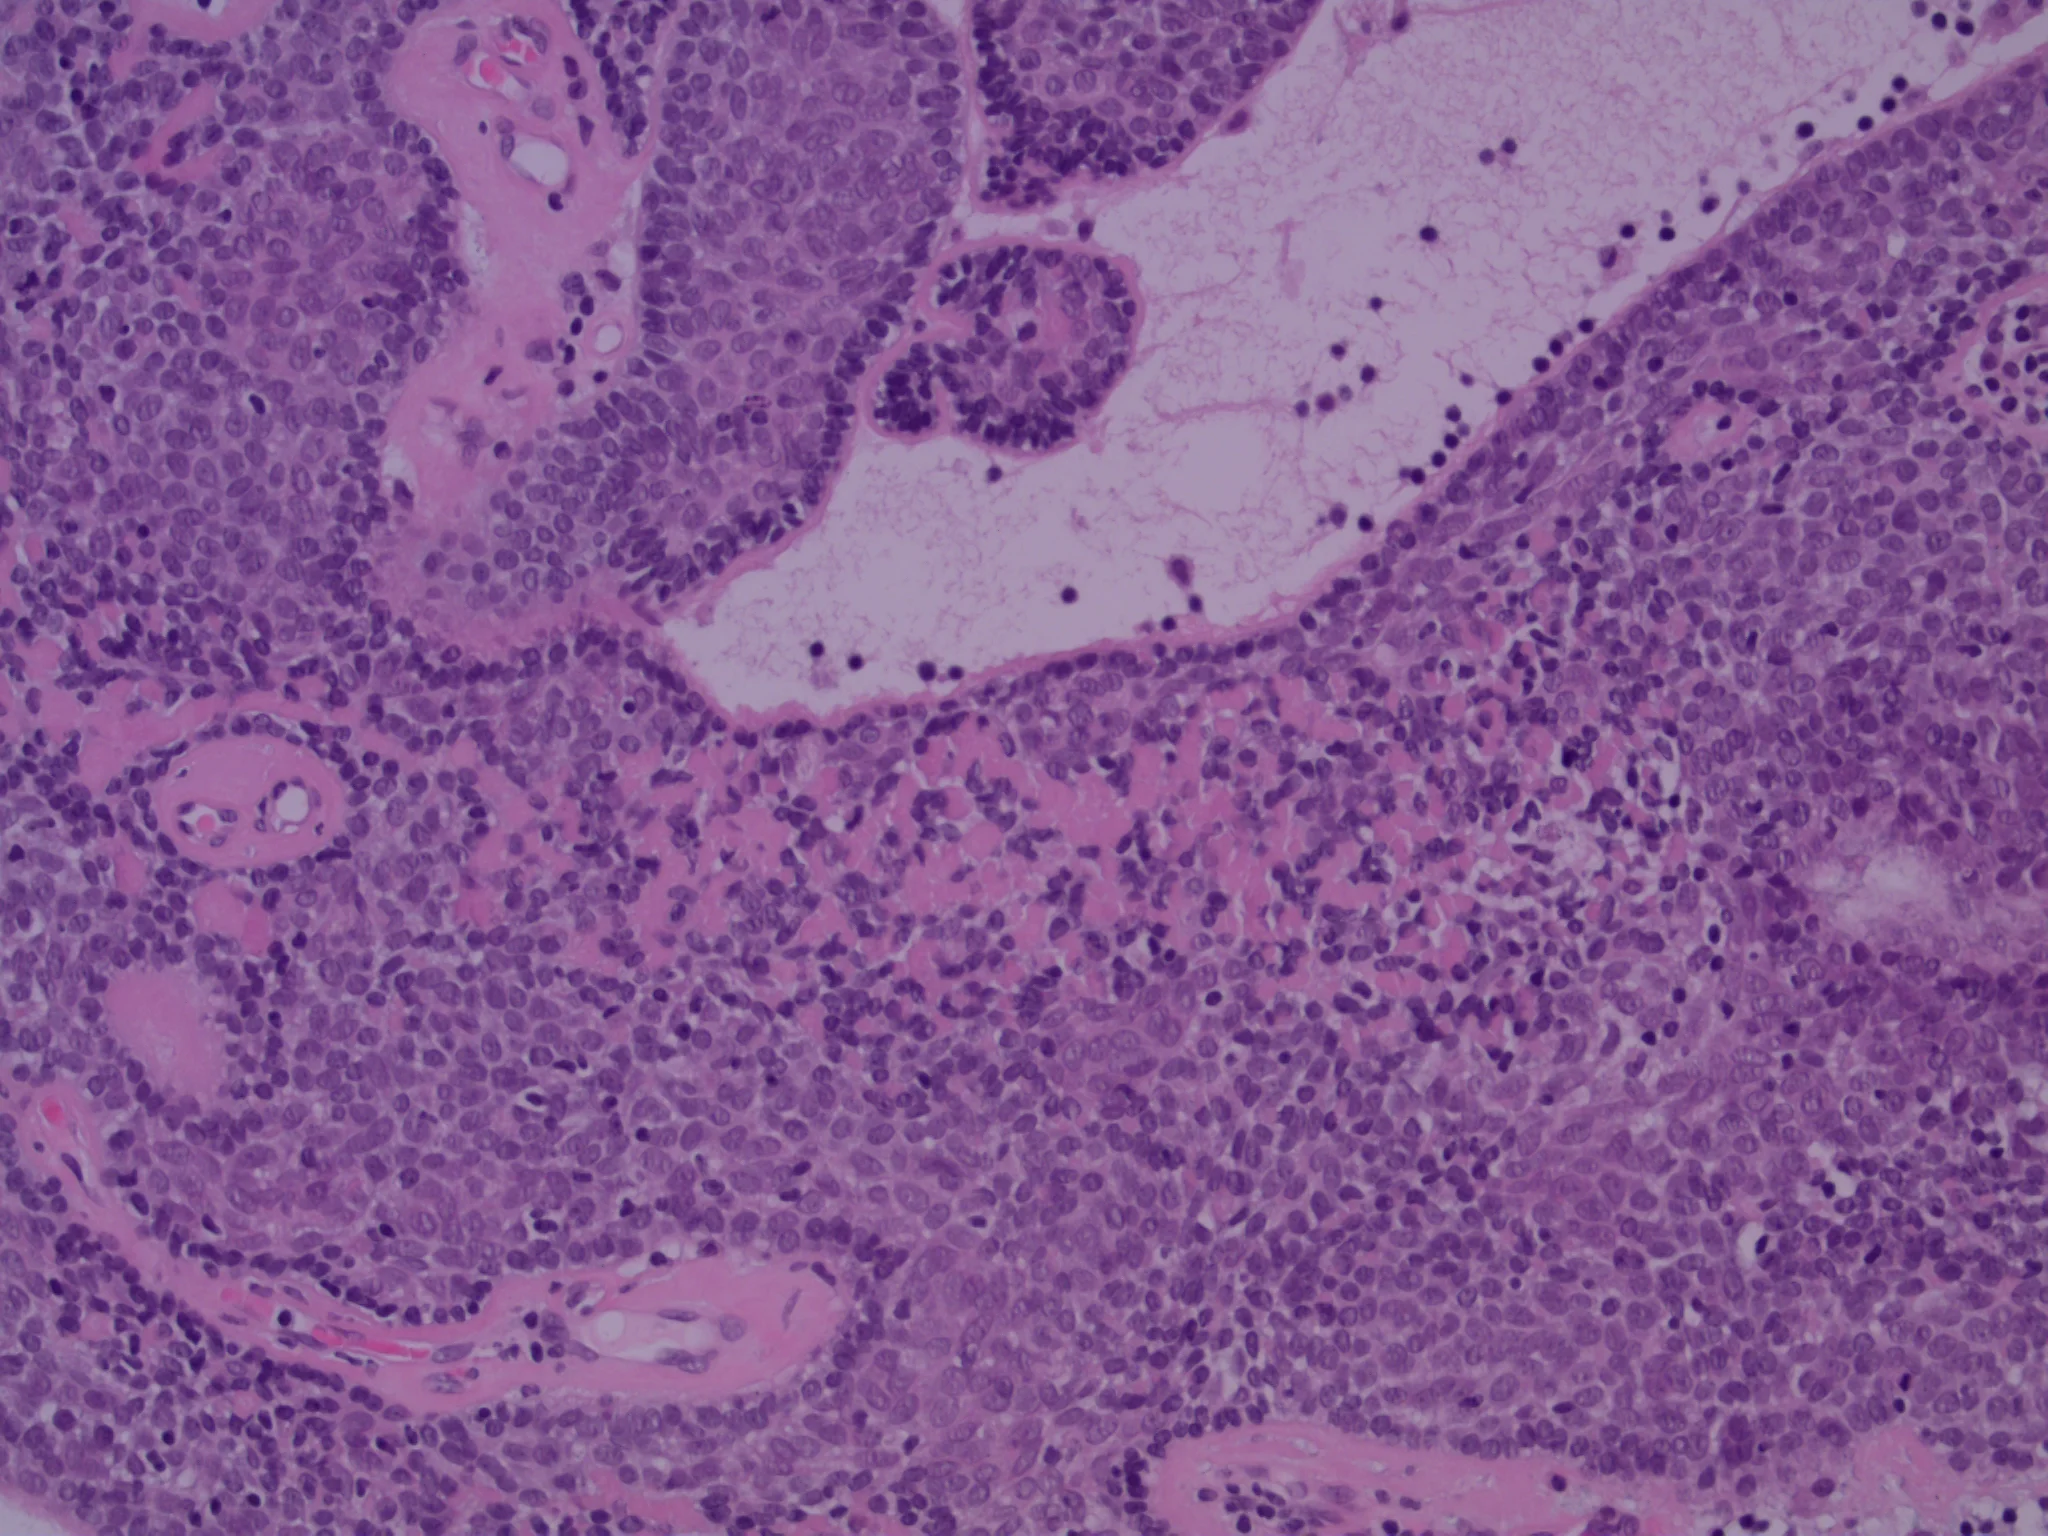

31 yo Indian man with multiple ?pilar cysts scalp. Clinical photos aren’t from our patient.